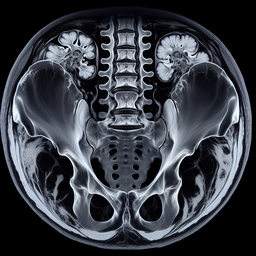

МРТ крижів і куприка

Магнітно-резонансна томографія (МРТ) крижів і куприка — це неінвазивний метод діагностики, що застосовується для детального обстеження цих зон. Він використовує магнітне поле і радіохвилі для створення високоякісних зображень м'яких тканин, м'язів, нервів і кісток.